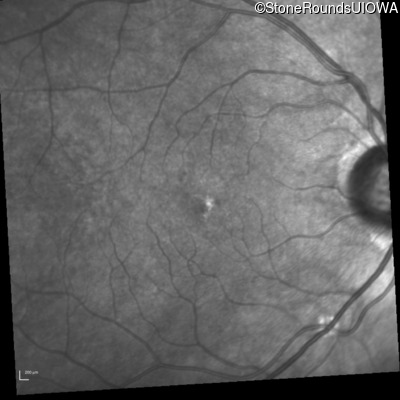

Infrared Fundus Photograph - Right - 20/20

Exemplar